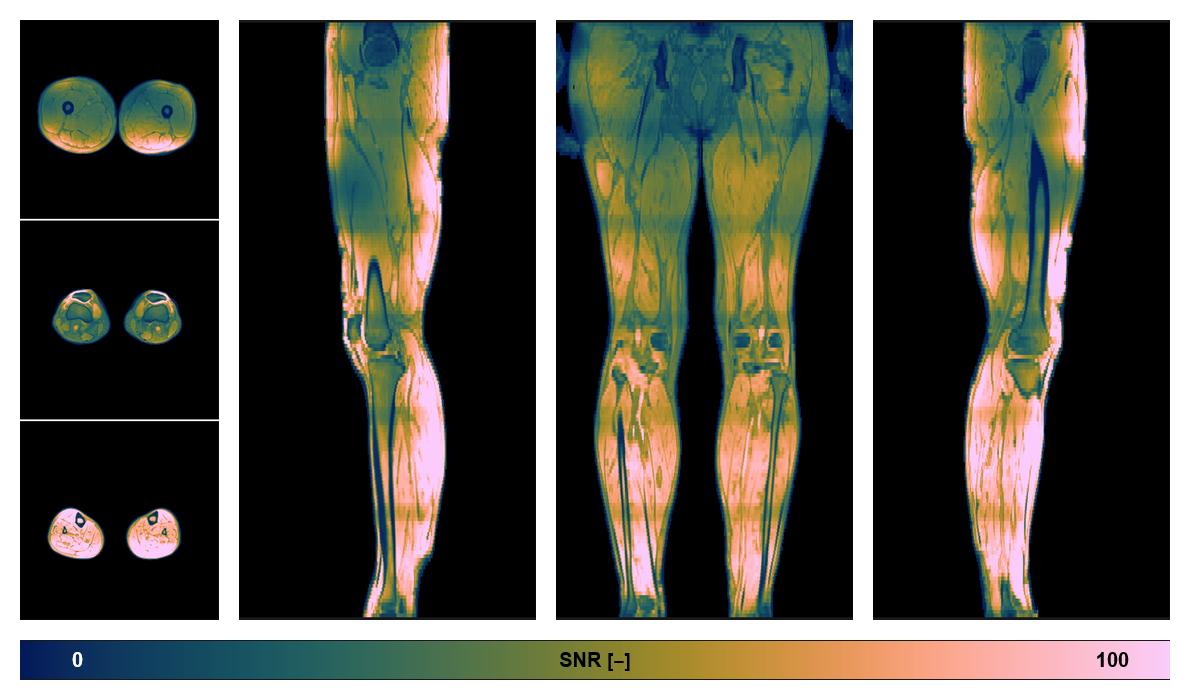

• SNR distribution

The SNR distribution of the dixon data.